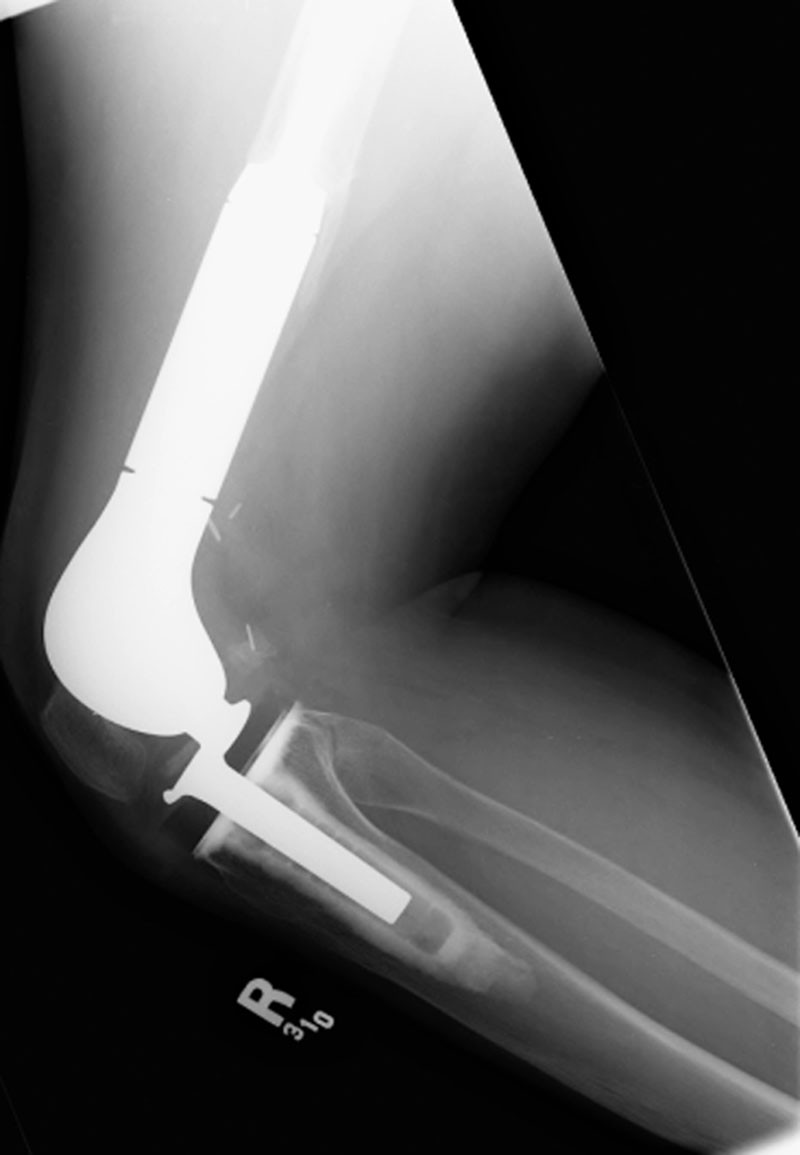

Rotating-hinge knee implant Rotating-hinge knee implant failure

Right knee revision arthroplasty Right knee revision implant Right knee revision implant failure Right knee revision implant failure

69 year-old man with revision of an infected right knee prosthesis (two left panels). A rotating-hinge knee implant was placed. Note the antibiotic beads about the medial aspect of the implant. The two fixation screws and wire are from prior surgery. There was implant failure with disruption of the implant six weeks later (two right panels).